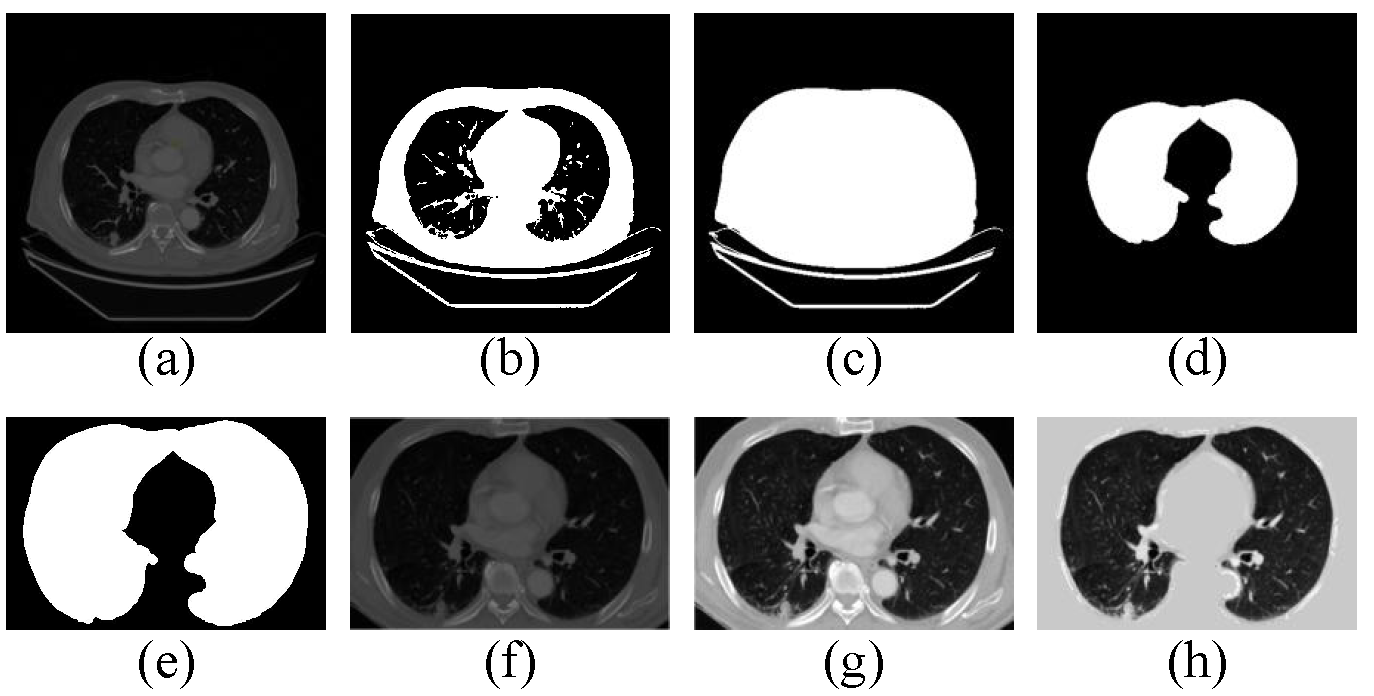

3.2.1. Preprocessing